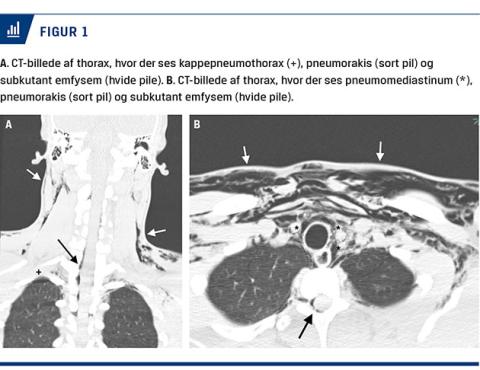

En 19-årig mand blev indbragt til akutmodtagelsen på Holbæk Sygehus med ambulance ledsaget af politi. Angiveligt var han, kort efter ankomst til sin partners hjem, blevet tiltagende udadreagerende og agiteret, hvorfor politi og ambulance var blevet tilkaldt til hjemmet. Det var uvist, hvad han havde lavet forud for ankomsten til partnerens hjem, men der var rejst mistanke om indtagelse af euforiserende stoffer, da pårørende angav, at han tidligere havde haft et forbrug af euforiserende stoffer. Ved den indledende undersøgelse fandt man svært dilaterede pupiller, gentagne kraftige Valsalvas manøvrer, krepitationer subkutant fra halsen og ned på thorax, normal hjerte- og lungestetoskopi, ingen synlige traumer på hoved, krop eller ekstremiteter og ingen klinisk mistanke om fraktur eller akut abdomen. Manden var vågen, men svarede ikke relevant på tiltale, kastede sig rundt i sengen og slog ud med armene. De vitale værdier var stabile. Syre-base-status viste respiratorisk alkalose. Urinscreening for rusmidler var negativ. På mistanke om pneumothorax blev der lavet røntgenoptagelse af thorax på stuen. Denne blev tolket som normal. Som led i videre udredning blev der foretaget CT af cerebrum, columna cervicalis og thoracalis, hvor man fandt en smal kappepneumonothorax, pneumomediastinum, pneumorakis og subkutant emfysem, der strakte sig fra m. masseter bilateralt til midt på thorax (Figur 1). Patientens pneumothorax blev konservativt behandlet, og han blev udskrevet uden videre behandling.